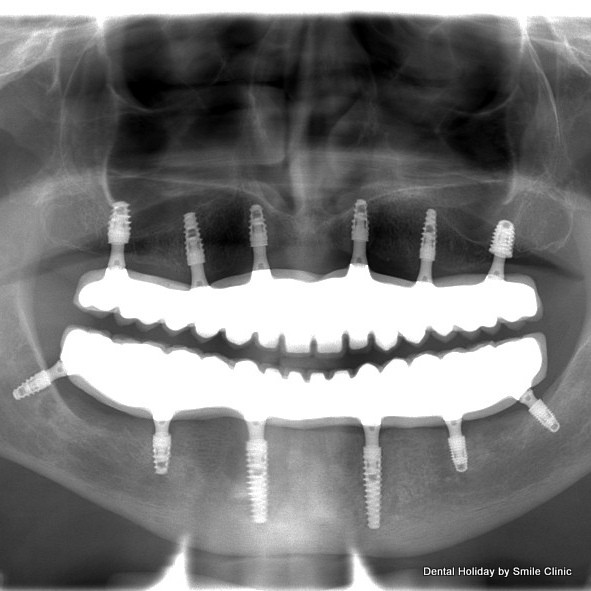

At the beginning of his first visit to Piešťany dental clinic, he had a consultation appointment with Dr Marek. The doctor suggested All on 6 dental implants treatment for him. In order to place the dental implants, bone graft on his upper jaw was needed. We made all necessary X rays and CT scans and started the treatment on the second day of his visit. The doctor took 2 of Alan’s remaining teeth out, did the bone graft and successfully put 6 dental implants in Alan’s upper jaw. The doctor put a healing abutment on each dental implant and temporary dental crowns were provided as well.

On the third day of Alan’s visit, we continued the treatment with his lower jaw. After the extraction of 6 teeth, Dr Marek put 6 dental implants in his lower jaw. The surgery took 4 hours in the dental chair and stage 1 of the All on 6 procedure for both jaws was completed. After a quick after-surgery check up on the next day Alan flew back to the UK.

On the third visit, we finished Alan’s dental treatment. We removed his temporary dental crowns and put 14 porcelain dental crowns on his upper jaw and 14 dental crowns on his lower jaw.